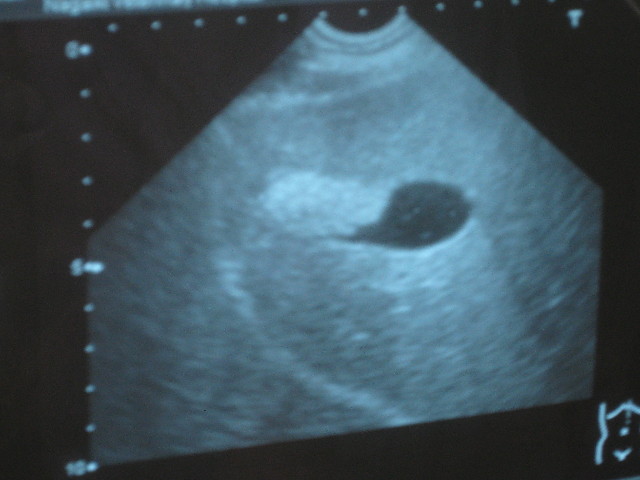

黒く写っているところが胆のう。

ちょっと場所を変えて、黒い胆のうの左の白っぽいのが胆泥。

胆泥は前より増えてしまっている。